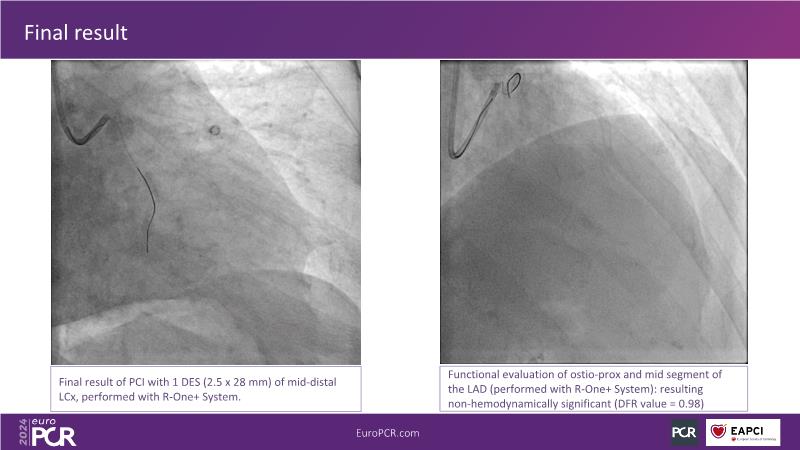

In this session, discover the effectiveness and safety of robotic PCI for both simple and complex lesions requiring additional devices like IVL, IVUS, laser, and FFR. Learn about the numerous benefits of robotics for patients and cathlab teams, including enhanced precision in wire navigation and stent positioning, full radioprotection, and reduced orthopedic injuries. Explore the growing interest in robotics within the interventional cardiology community, anticipate future technical advancements, and understand how AI will accelerate the integration of robotics and vice versa.

- To learn about a robotic PCI step-by-step from real-life experience